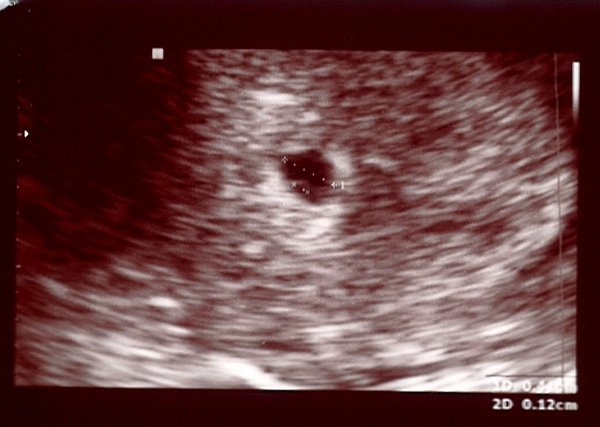

Ma voltunk uh-on és van eg 4 mm-es petezsék, benne 1.2 mm-es szikkel.

Múlt héten volt 4 mm-es petezsákunk és 1.2 mm-es szikhólyagunk.